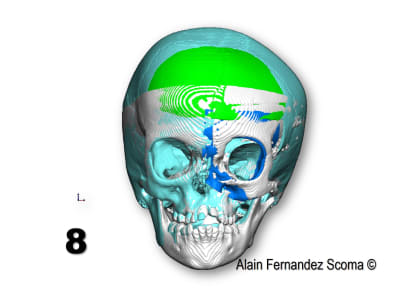

Tien un exemple d'une commande par un Professeur en maxillo- qui me demande : " Alain, tu peux étudier comment segmenter ce massif facial (1) pour reconstruire une forme correcte (2)". Le jour de chirurgie (3) ils sont utilisé un guide de coupe (4)pour tracer les segments et découper la calotte crânienne (5)l'arcade orbitaire... et réorganiser (6) les tronçons. Le scan de contrôle (7) superposé sur l'étude (8) montrent la pertinence du partage. Il y a une découpe dont le tracé à était modifié par rapport à l'étude ce qui m'a fait plaisir de voir justesse d'analyse du chirurgien.